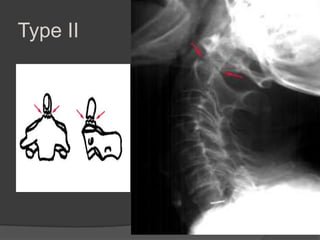

Classification

Type I: Avulsion of the tip of

the dens where it is attached

to C1.

This is a rare fracture.

It is potentially stable.?

Type II: Through the base of

the dens.

Most common fracture.

Always unstable and poor

healing.

Type II